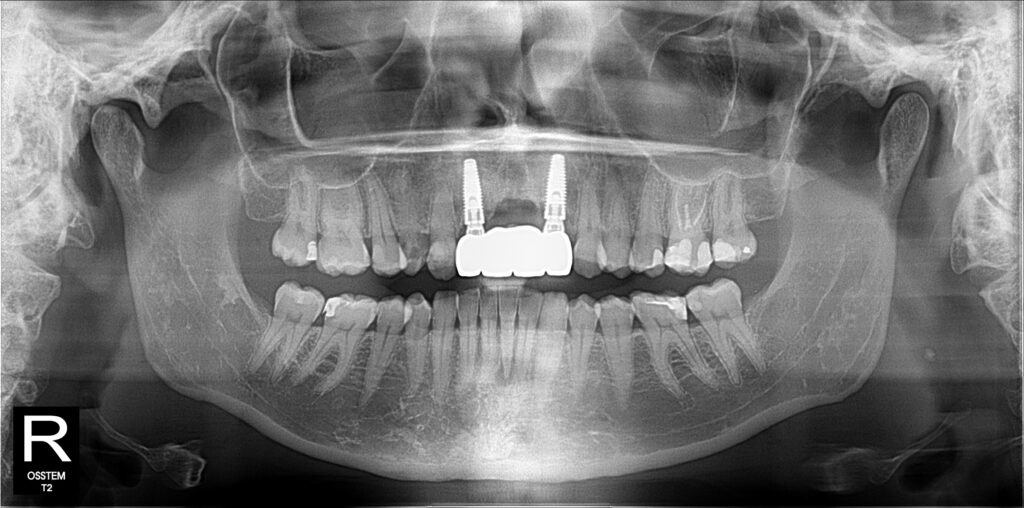

A selection of partial arch fixed implant bridge patients